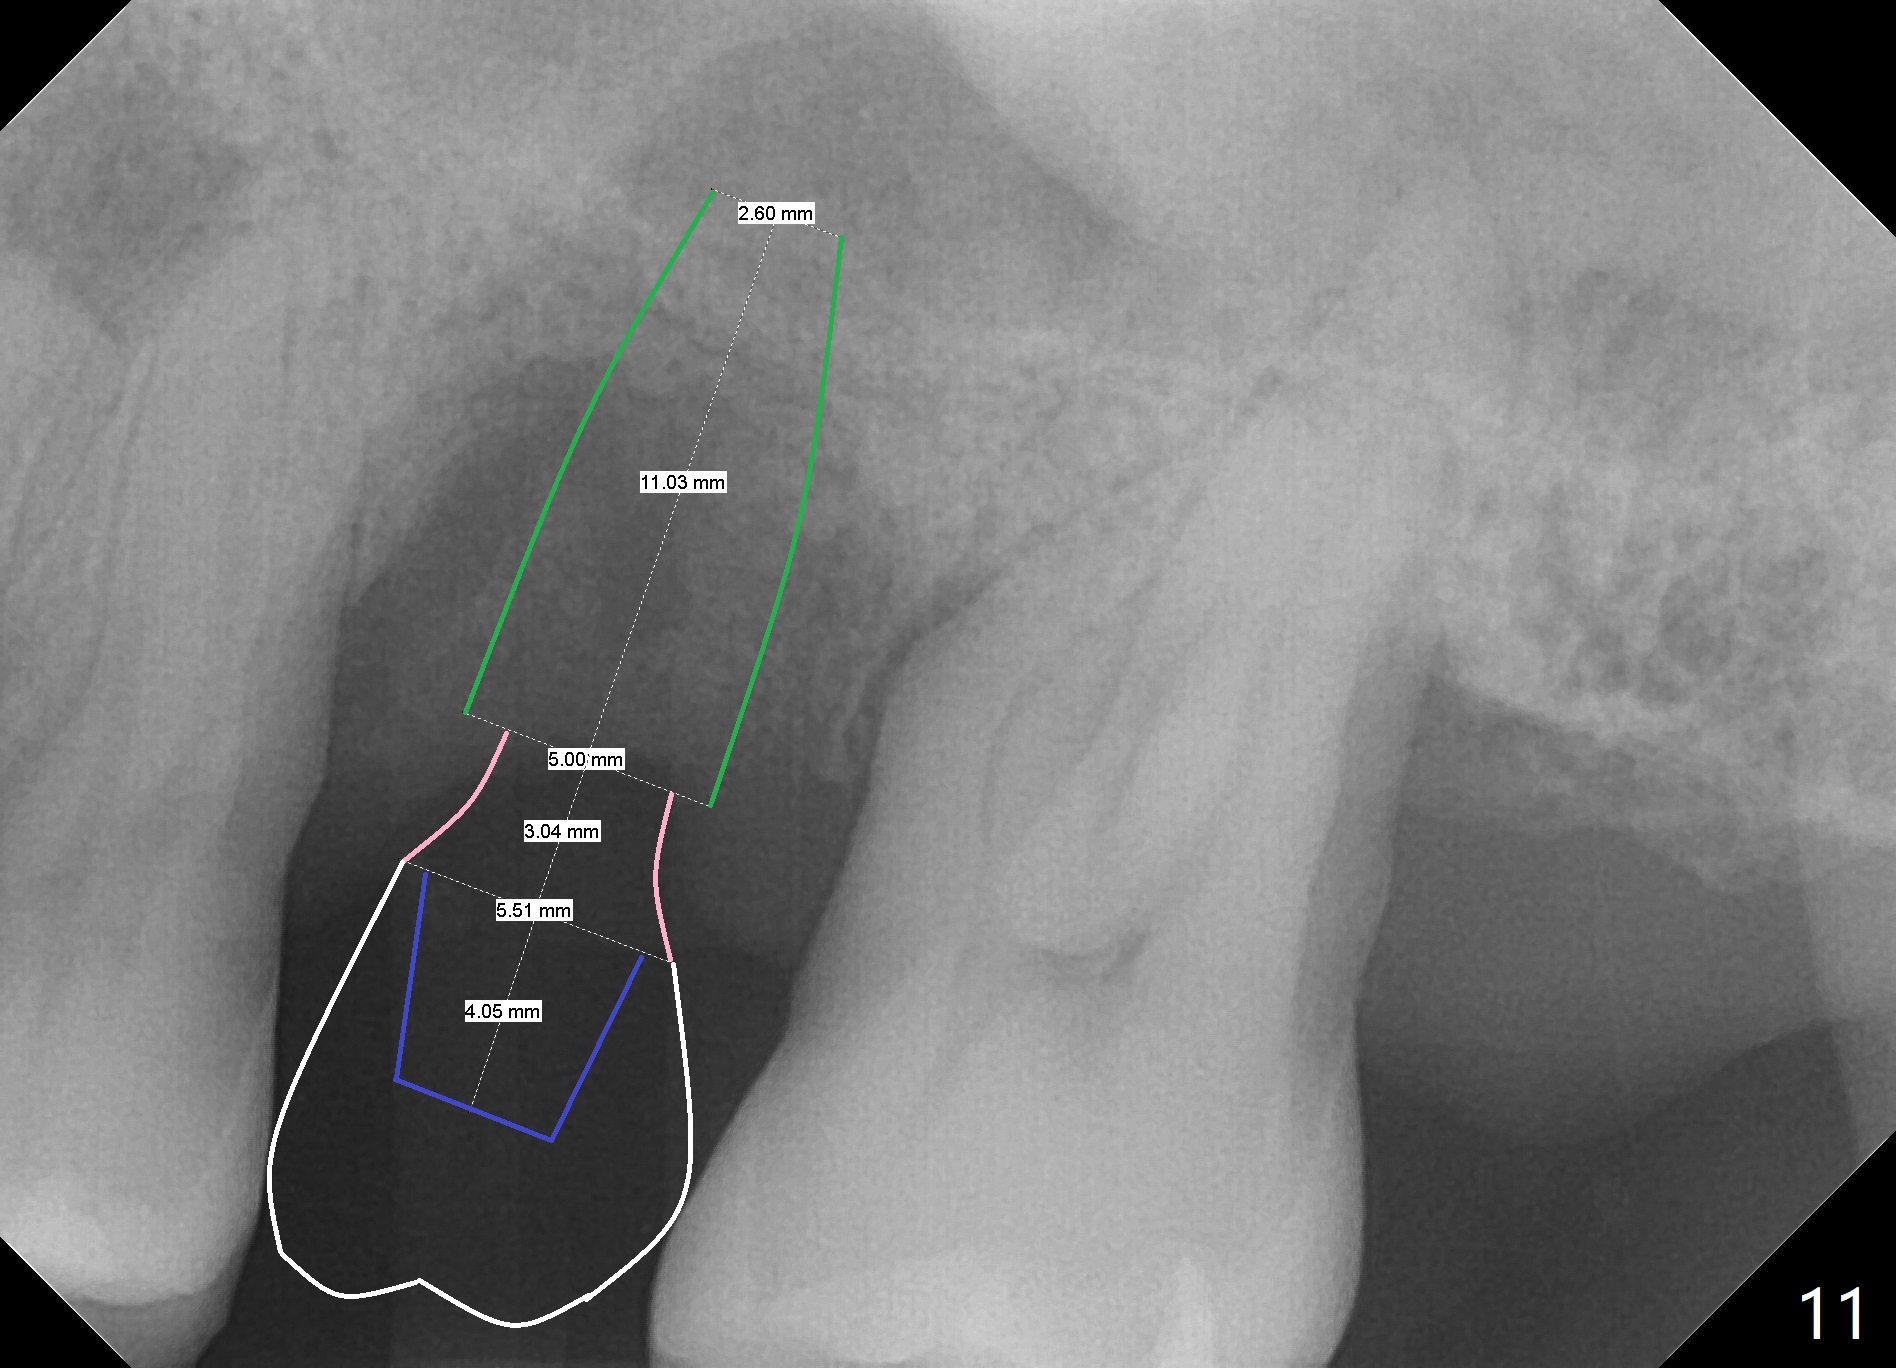

When the tooth #14 is extracted, the buccal plate is lost, while the apex of the palatal socket is perforated. The palatal slope of the septum appears to be a suitable site for osteotomy, but the depth seems to be 2 mm. After sequential osteotomy until 5.3 mm with drills, a 5.9 mm SM tap obtains stability (Fig.2). A 5.9x8 mmm implant is placed with barely sufficient stability after 1 piece of PRF membrane and VeraGraft (Fig.2-4). The implant rotates and dislodges when an abutment is being placed. Neither do 6-8x17 mm Tatum taps achieve primary stability. Socket preservation is performed, followed by periodontal dressing (Fig.5). Primary stability might have been obtained if a smaller IBS implant with fins were placed in the palatal socket. The periodontal dressing has dislodged 1 week postop; the socket appears healing (Fig.6,7). Bone graft seems to be minimal or bone density of the graft is low (Fig.8). The socket heals with a wide ridge 2 months post socket preservation, but the tooth #15 seems to be buccal (Fig.9) and mesial (Fig.10) shift. After use of Magic Split and Expanders (until 3.8 mm for 13 mm), try 5 mm dummy implant (Fig.11). If 6 mm one fails to achieve stability substantially, switch to 7 mm Tatum tapered tap provided there is enough mesiodistal space (use 8 mm implant positioner to gauze the space beforehand (preop)). Consider using Vanilla (not Vera) Graft to fill in the gap between implant and osteotomy. When primary stability is obtained, place a nonfunctional provisional to prevent further shifting (Fig.11 white outline). After osteointegration, use the provisional (reline and separator) to distalize the tooth #15.